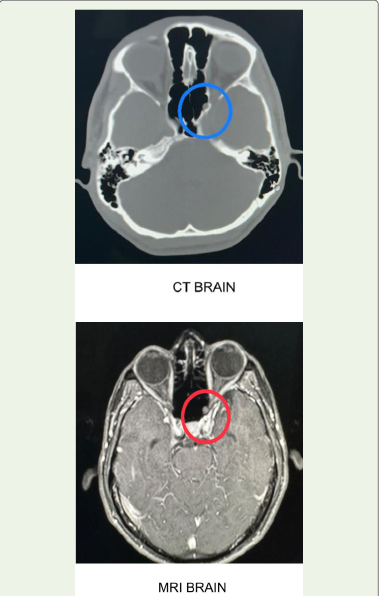

• CT Brain:

Revealed focal thinning and defect in the superolateral wall of the

• MRI Brain:

Demonstrated encephalocele abutting the infraorbital optic nerve segment, consistent with a Type II Sternberg’s canal defect.